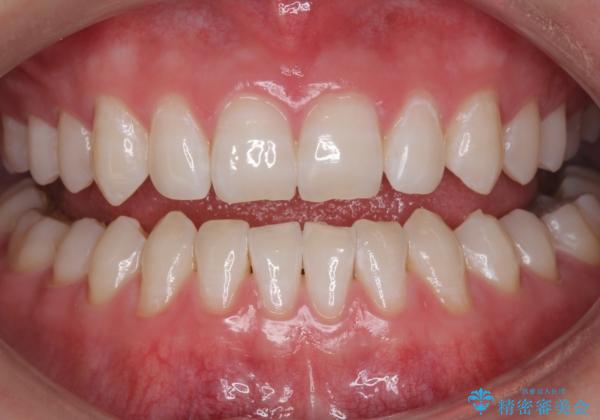

モチベーションの上がる白い歯に

- 元の色は普通より少し黄色めの白さでした。お口の中は、プラーク等付着してなくてきれいな状態でした。

ホワイトニングエクセレントコースで3回照射の施術をしました。